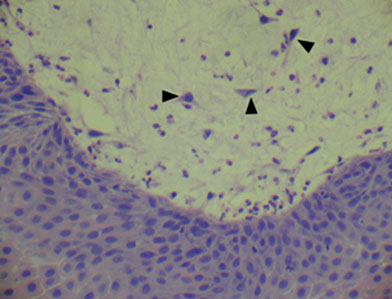

Rhinoscleroma c subepithelial histiocytes`

Micro: inc lymphs, Russell bodies, histiocytes (Mikulicz cells) have organisms ingested

IHC: Warthin Starry silver stain can show intra-histiocytic organisms (gram negative bacteria)